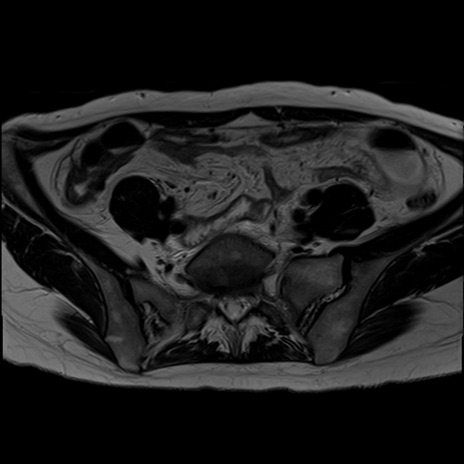

症例39 T2WI(横断像)

MRI(4日後)